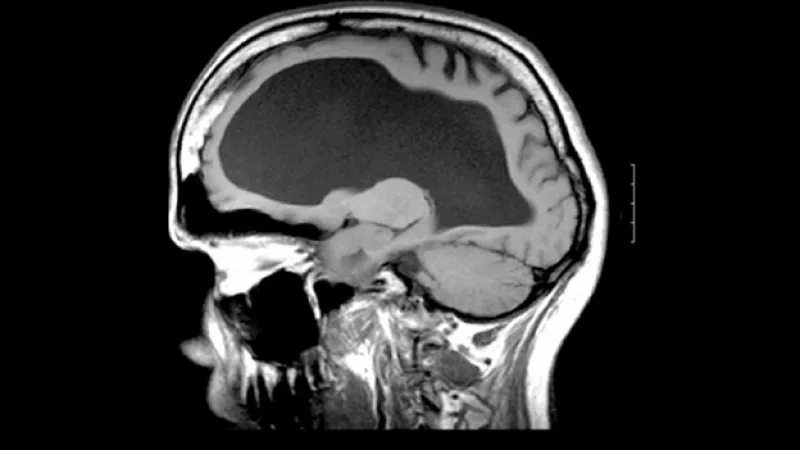

hidrocefalia tomografia

Un grupo de científicos europeos y americanos están más cerca de encontrar una cura para la hidrocefalia, un trastorno con el que nacen casi tres millones de niños al año, sustituyendo las células dañadas de la corteza cerebral por células madre mediante cirugía en el periodo fetal.

El experto explicó que  la hidrocefalia se produce por la acumulación del líquido cefalorraquídeo dentro del cerebro , aunque matiza que "no es solo un trastorno líquido, sino de todo el cerebro, ya que se ha producido un daño cerebral que, incluso, es previo a la hidrocefalia".

El especialista aclaró que "en condiciones normales el líquido cefalorraquídeo está en permanente circulación desde el sitio donde se produce, los ventrílocuos laterales, hasta el lugar donde se absorbe".

"Sin embargo si hay dificultad en la circulación o producción del líquido, este se acumula en las cavidades ventriculares y se produce el agrandamiento de la cabeza y, entonces, estamos ante un caso de hidrocefalia congénita fetal", añadió.